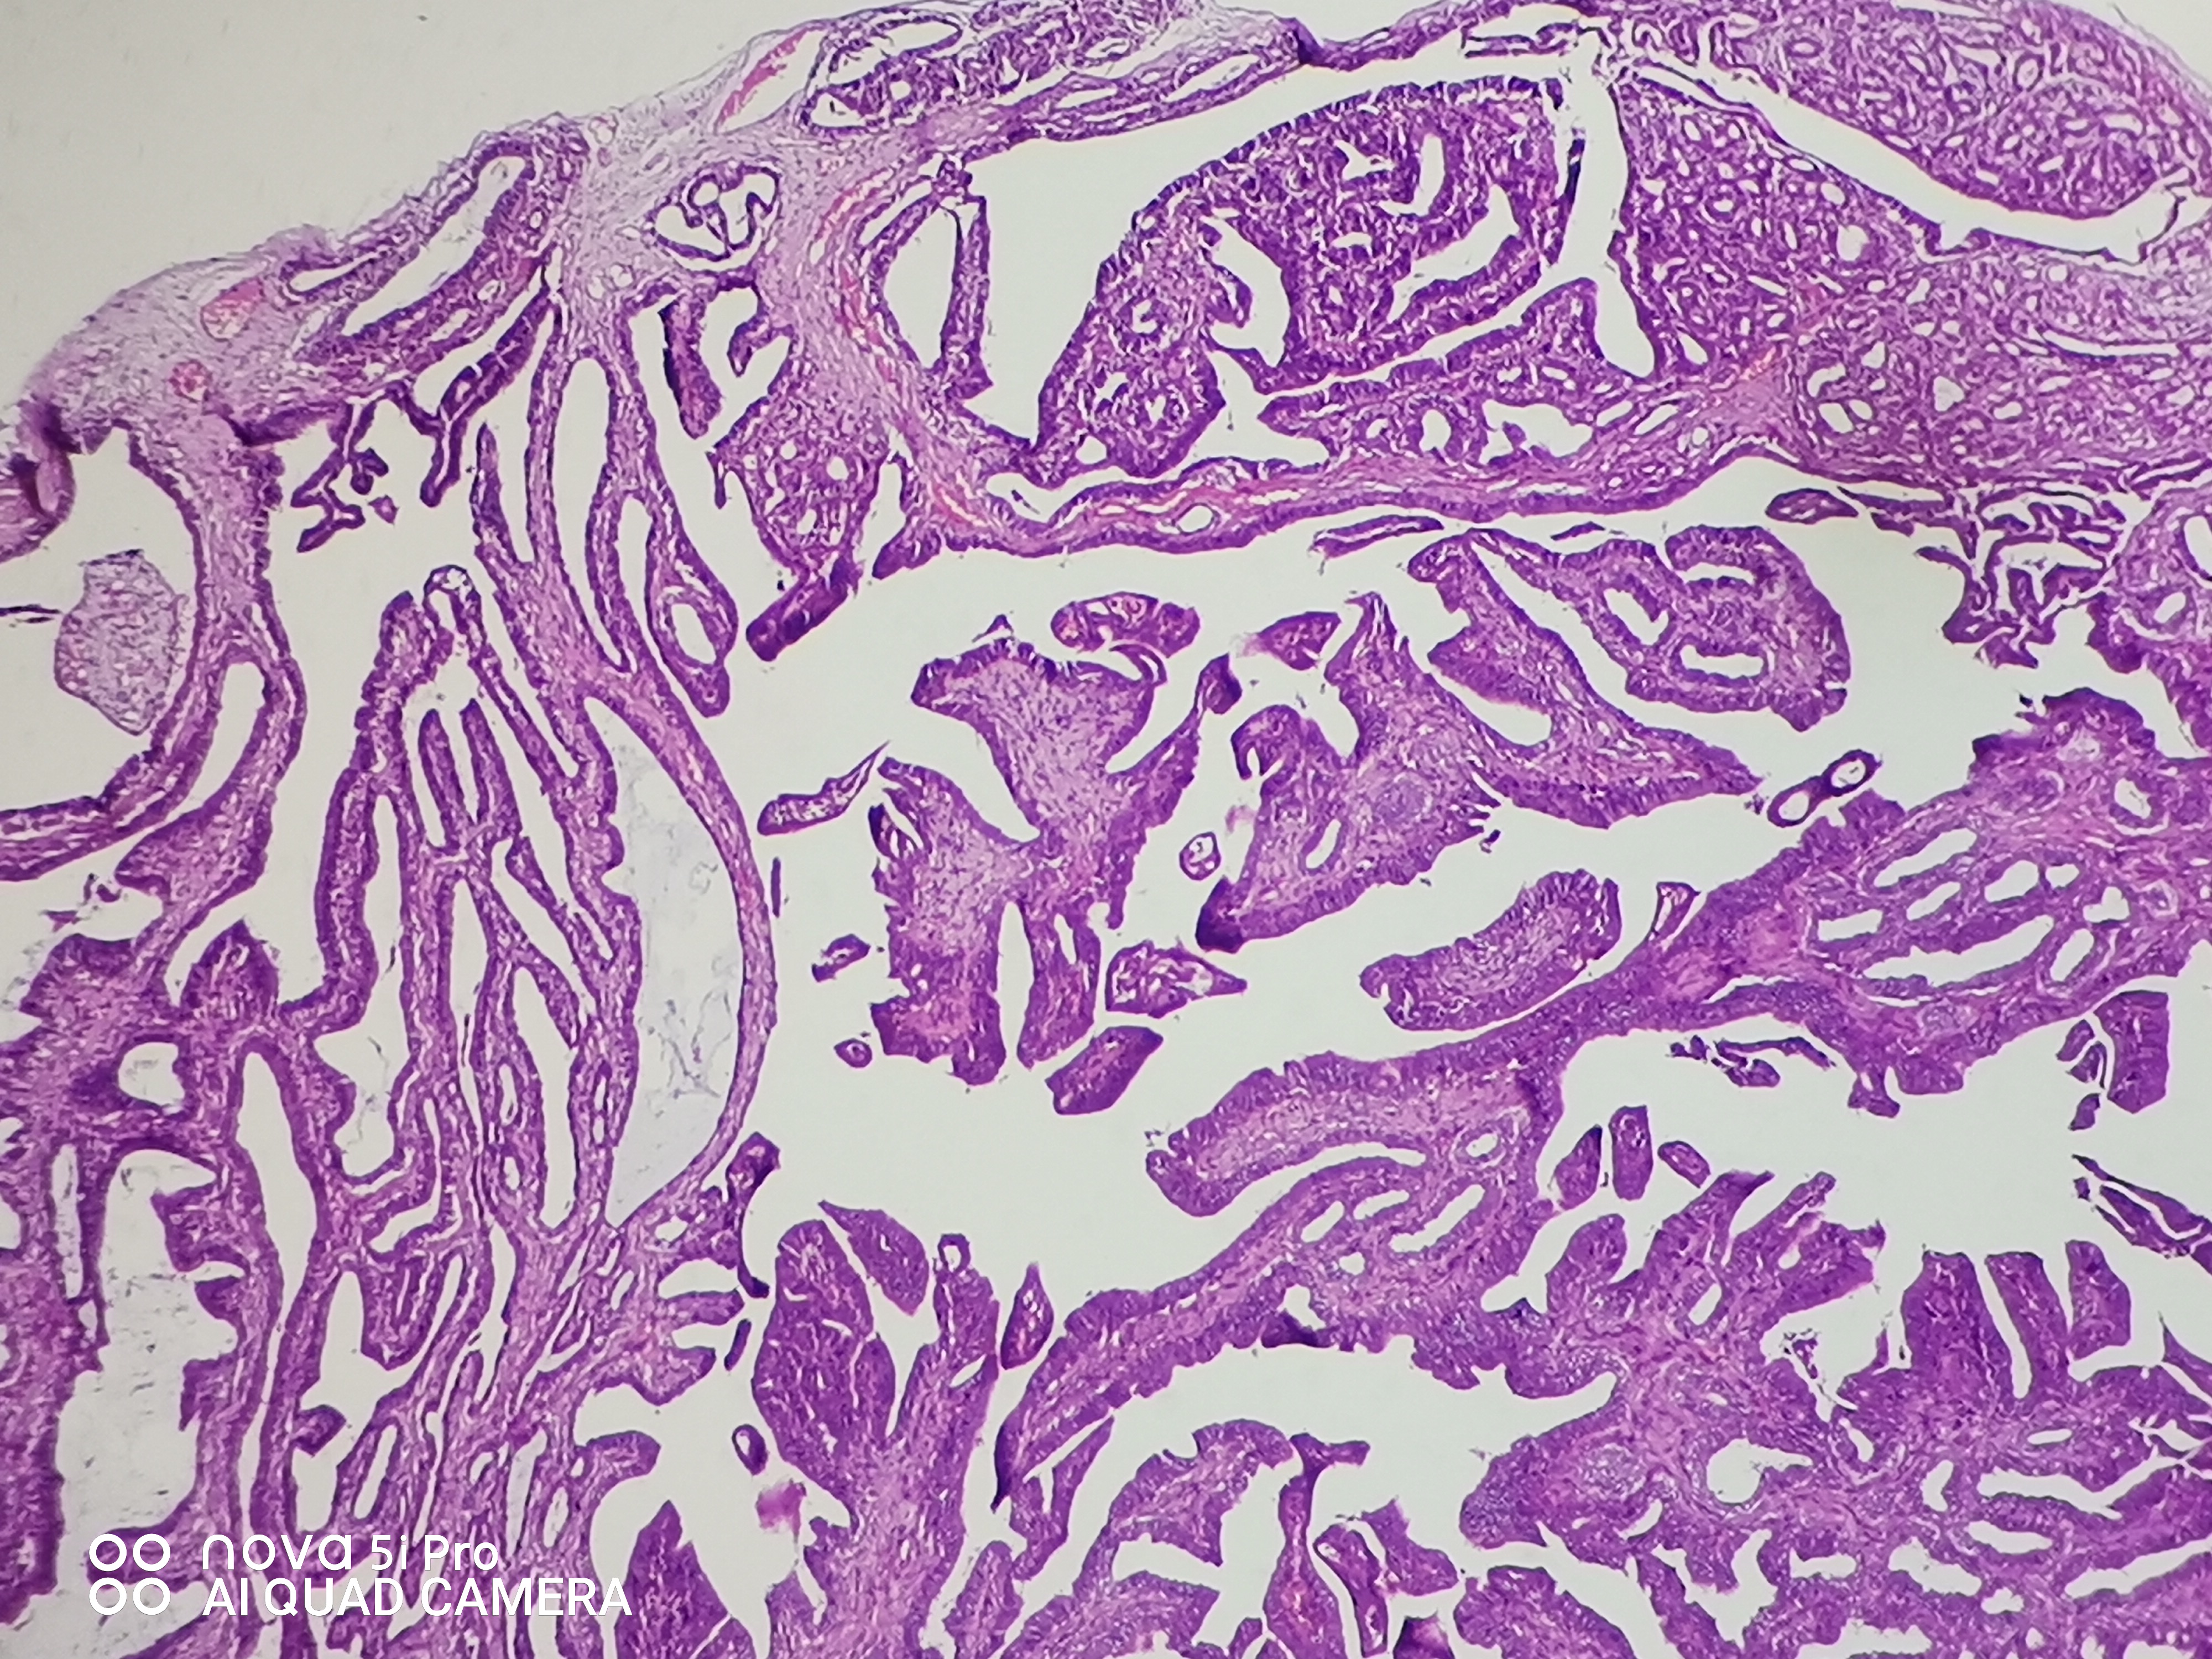

性别年龄41岁临床诊断混合痔,肛门肿块性质待查。

一般病史肛门肿块反复脱出5年,加重2月余。

标本名称肛门肿块

大体所见组织一块,大小约0.7*0.5*0.5cm,对半切开,实性灰白质中,全取。

高级别乳头状肿瘤

考虑:癌变!

乳头状汗腺瘤?

• 云子:  如果是肠上皮的话会有纤毛细胞,会有杯状细胞。杯状细胞的消失对应的是高级别肠上皮细胞病变,然而切片不支持高级别。女性外阴、肛门的这种乳头状生长模式十断头分泌现象,我更首先考虑乳头状汗腺瘤。个人意见,仅供参考!

图1可见断头式分泌,需要鉴别 汗腺肿瘤,标一下CK7.CK20.SATB-2.和P63。

这个病例的医生刚刚打电话联系我了,经省里专家远程会诊也是考虑乳头状汗腺瘤伴轻一中度非典。